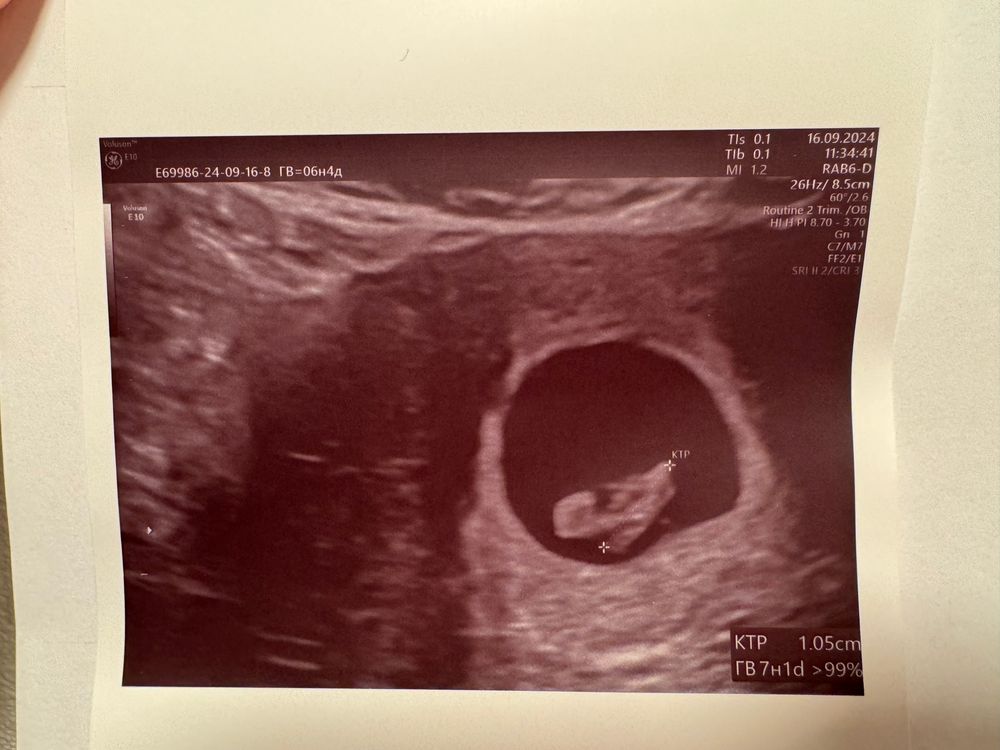

Поздравляю вас❤️ Какой у вас срок на момент прохождения узи?

Счастье, спасибо☺️ по месячным 6н 4д, по ктр поставили 7н 1д. Овуляция видимо ранняя